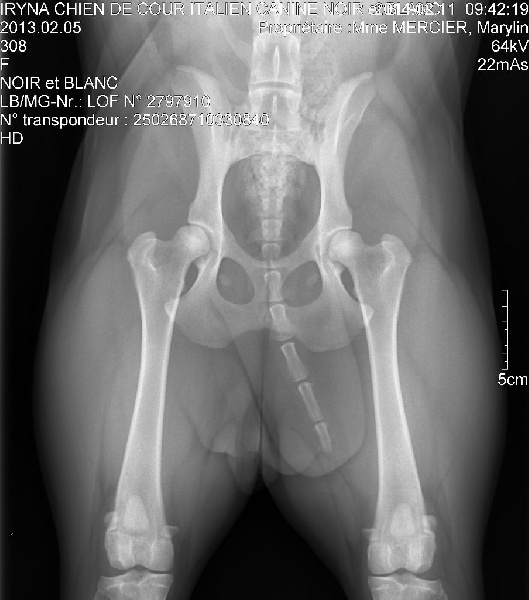

250268710330840

27979